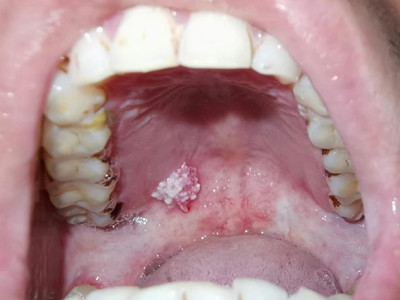

口腔尖锐湿疣症状图片

口腔尖锐湿疣好发于舌、牙龈、腭等部位,表现为单个或多个无痛性的疣状结节,有蒂或无蒂,可逐渐增大或融合,形成菜花状、乳头状赘生物,颜色呈肉色或苍白色,患者可有异物感。